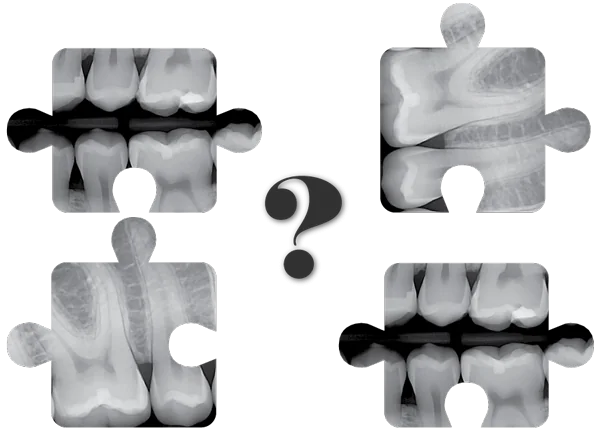

Will DentiMax Dental Sensors Work in Eaglesoft ®/ Patterson ® Imaging?